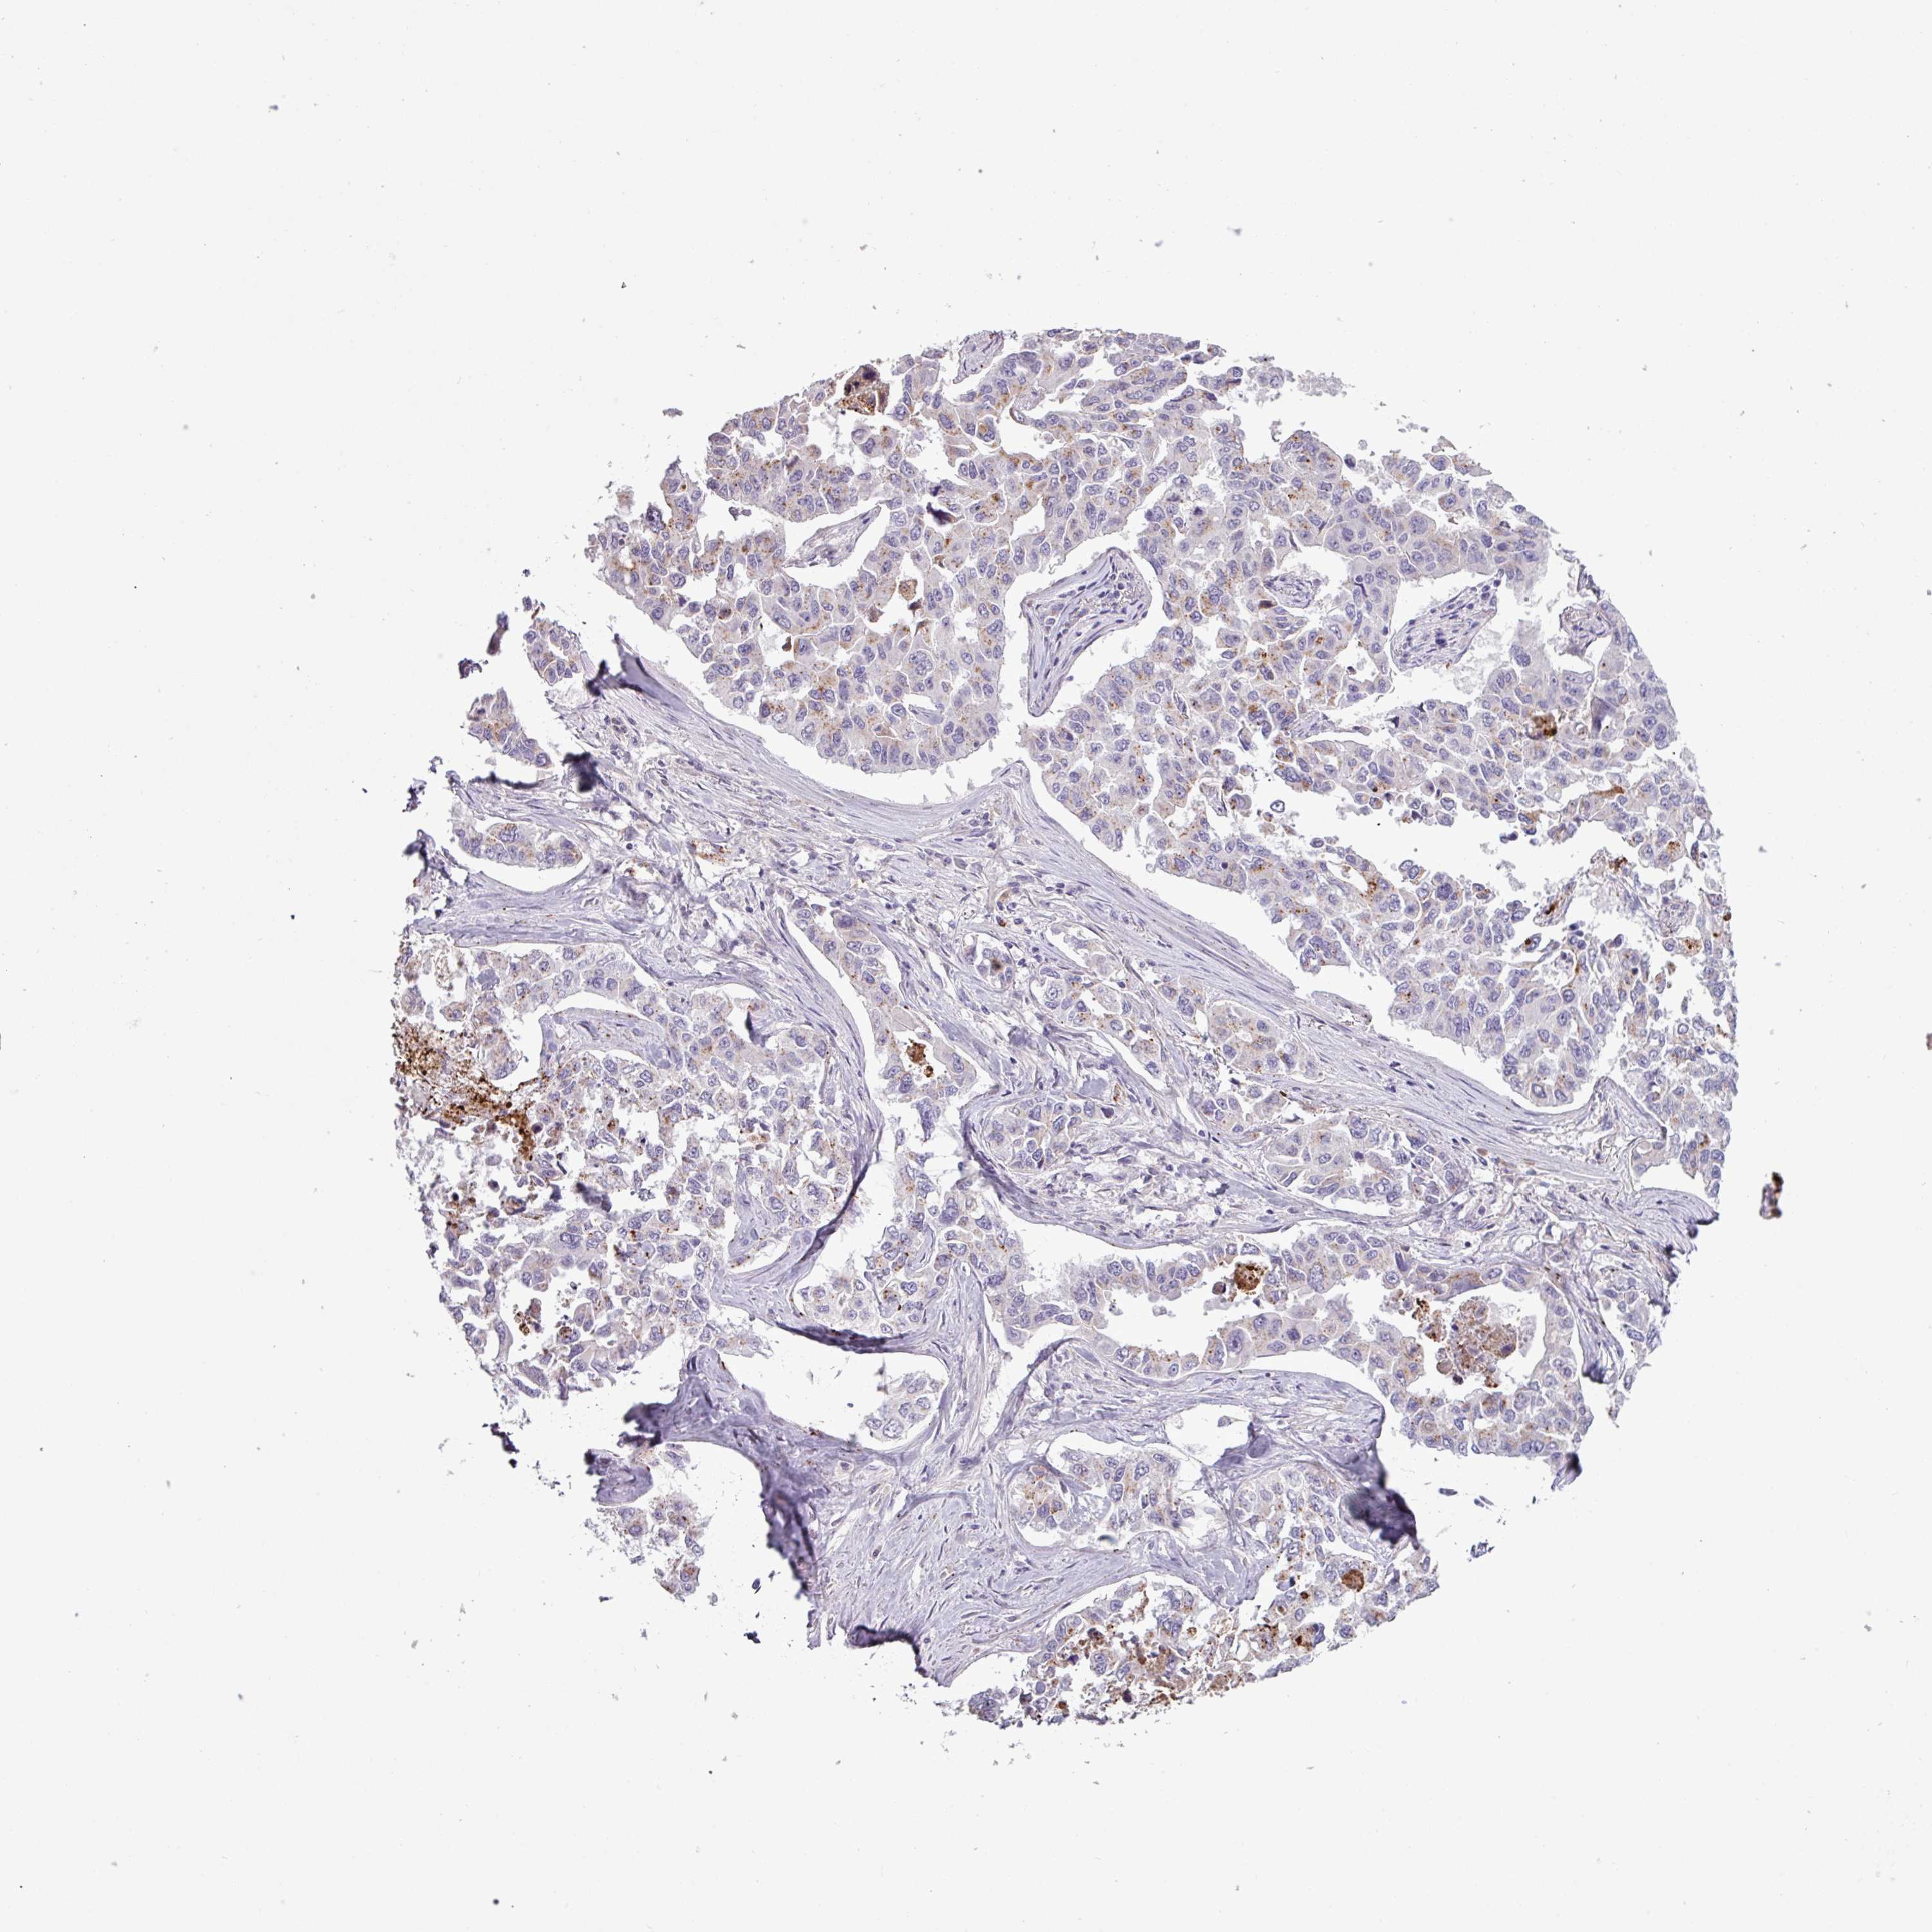

CANCER LUNG CANCER Show tissue menu

LUAD TCGA LUAD VALIDATION LUSC TCGA LUSC VALIDATION PROTEIN LUAD CPTAC PROTEIN LUSC CPTAC PROTEIN EXPRESSION